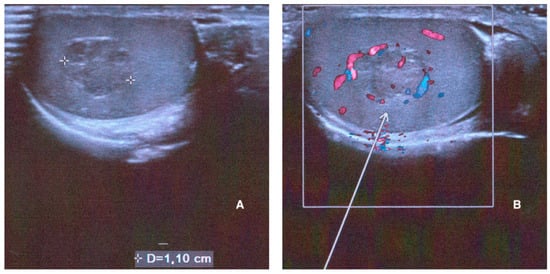

A testicular ultrasound was then performed. The findings were as follows: testicles in situ, with a volume of about 12 mL bilaterally. No significant epididymal ultrasound alterations, nor signs of hydrocele or varicocele were evident. A solid vascularized 11 mm × 8 mm hypoechoic mass was found in the right testicle (Figure 1).

Figure 1. Right testicle ultrasound performed at baseline showing a solid mass with a maximum diameter of 1.10 cm on B-mode US (A) and its hypervascularization on color Doppler ((B), white arrow).